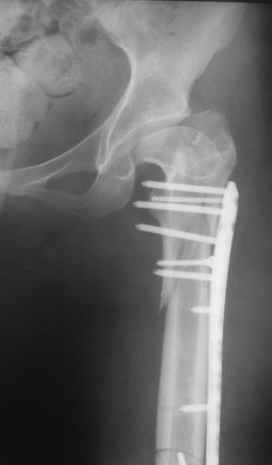

Уважаемые коллеги, приношу извенения за молчание. Готовили материал и боялись писать раньше времени. Все хотели убедиться в том, что после операции все будет спокойно. Спасибо за отклики и советы. К сожалению, гамма-гвоздя, штифтов с возможностью установки более 2-х блокирующих винтов у нас нет. Зато нашли достаточно длинную пластину с угловой стабильностью. После проведения предоперационной подготовки и планирования выполнили остеосинтез. В условиях рентгеноперационной, после репозиции дистрактором из одного разреза 5см в проксимальном отделе подкожно установили пластину. Пришлось выполнить дополнительный разрез до5см в проекции перелома диафиза в средней трети, из которого удалось репонировать перелом и выполнить фиксацию стягивающим винтом. Затем все завершилось наложением пластины с угловой стабильностью. Пластина оказалась достаточно длинной, что позволило перекрыть все переломы с фиксацией каждого отломка минимум 5-ю винтами. Синтез достаточно стабилен. Пациентка активизирована на 3-и сутки(снимки прилагаются). В настоящий момент пациентка выписана на амбулаторное лечение. Еще раз, огромное спасибо всем за помощь в выборе тактики и просто совете. С уважением Украинский Е.

Прошу прощения, со снимками глюк произошел. Высылаю. С уважением Евгений У.

Получилось очень симпатично, мои поздравления. А можно фото конечности без наклеек посмотреть?

И межфрагментарный винт на диафизе - так ли он нужен при выбранном варианте остеосинтеза с относительной стабильностью?